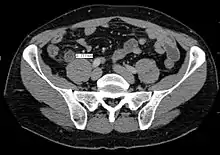

In children the clinical examination is important to determine which children with abdominal pain should receive immediate surgical consultation and which should receive diagnostic imaging.[42] Because of the health risks of exposing children to radiation, ultrasound is the preferred first choice with CT scan being a legitimate follow-up if the ultrasound is inconclusive.[43][44][45] CT scan is more accurate than ultrasound for the diagnosis of appendicitis in adults and adolescents. CT scan has a sensitivity of 94%, specificity of 95%. Ultrasonography had an overall sensitivity of 86%, a specificity of 81%.[46]

Computed tomography

Where it is readily available, computed tomography (CT) has become frequently used, especially in people whose diagnosis is not obvious on history and physical examination. Although some concerns about interpretation are identified, a 2019 Cochrane review found that sensitivity and specificity of CT for the diagnosis of acute appendicitis in adults was high.[51] Concerns about radiation tend to limit use of CT in pregnant women and children, especially with the increasingly widespread usage of MRI.[52][53]

The accurate diagnosis of appendicitis is multi-tiered, with the size of the appendix having the strongest positive predictive value, while indirect features can either increase or decrease sensitivity and specificity. A size of over 6 mm is both 95% sensitive and specific for appendicitis.[54]

However, because the appendix can be filled with fecal material, causing intraluminal distention, this criterion has shown limited utility in more recent meta-analyses.[55] This is as opposed to ultrasound, in which the wall of the appendix can be more easily distinguished from intraluminal feces. In such scenarios, ancillary features such as increased wall enhancement as compared to adjacent bowel and inflammation of the surrounding fat, or fat stranding, can be supportive of the diagnosis. However, their absence does not preclude it. In severe cases with perforation, an adjacent phlegmon or abscess can be seen. Dense fluid layering in the pelvis can also result, related to either pus or enteric spillage. When patients are thin or younger, the relative absence of fat can make the appendix and surrounding fat stranding difficult to see.[55]